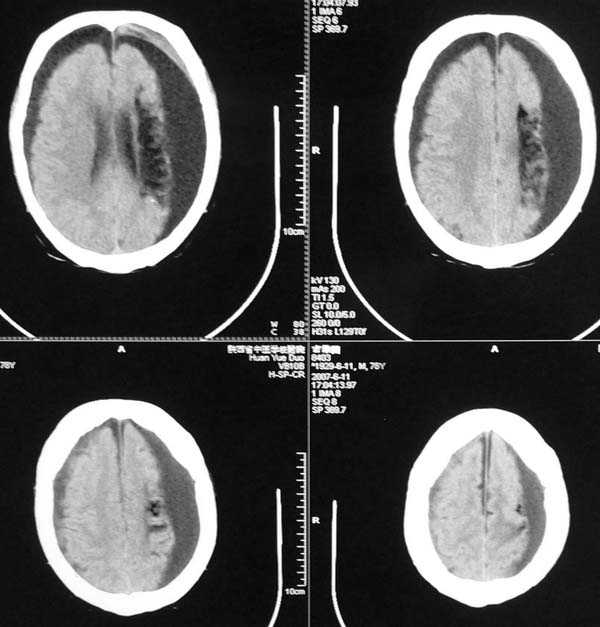

以下是引用star--868在2007-6-15 20:54:00的发言:[br]1.左侧额颞顶部亚急性硬膜下血肿并继续出血 双侧额颞顶部硬膜下积液;[br]2.左颞枕叶、左基底节区脑软化-左侧大脑中动脉栓塞;[br]双侧额颞顶部硬膜下积液应和治疗期间应用高渗脱水剂相鉴别:停用甘露醇后硬膜下积液会逐渐吸收减少,而单纯硬膜下积液无此改变和/或逐渐增多。

以下是引用狙击手在2007-6-15 21:15:00的发言:[br]软化灶就不必说了,主要是混和性血肿的渐变过程。

以下是引用老爱克斯新网客在2007-6-15 20:40:00的发言:[br]1左侧颞叶软化灶,2双侧硬膜下水瘤,3左册硬膜下血肿(多次少量出血),

以下是引用还珠格格在2007-6-16 7:07:00的发言:[br]支持.左侧额颞顶部亚急性硬膜下血肿并继续出血 双侧额颞顶部硬膜下积液;[br]2.左颞枕叶、左基底节区脑软化-左侧大脑中动脉栓塞;